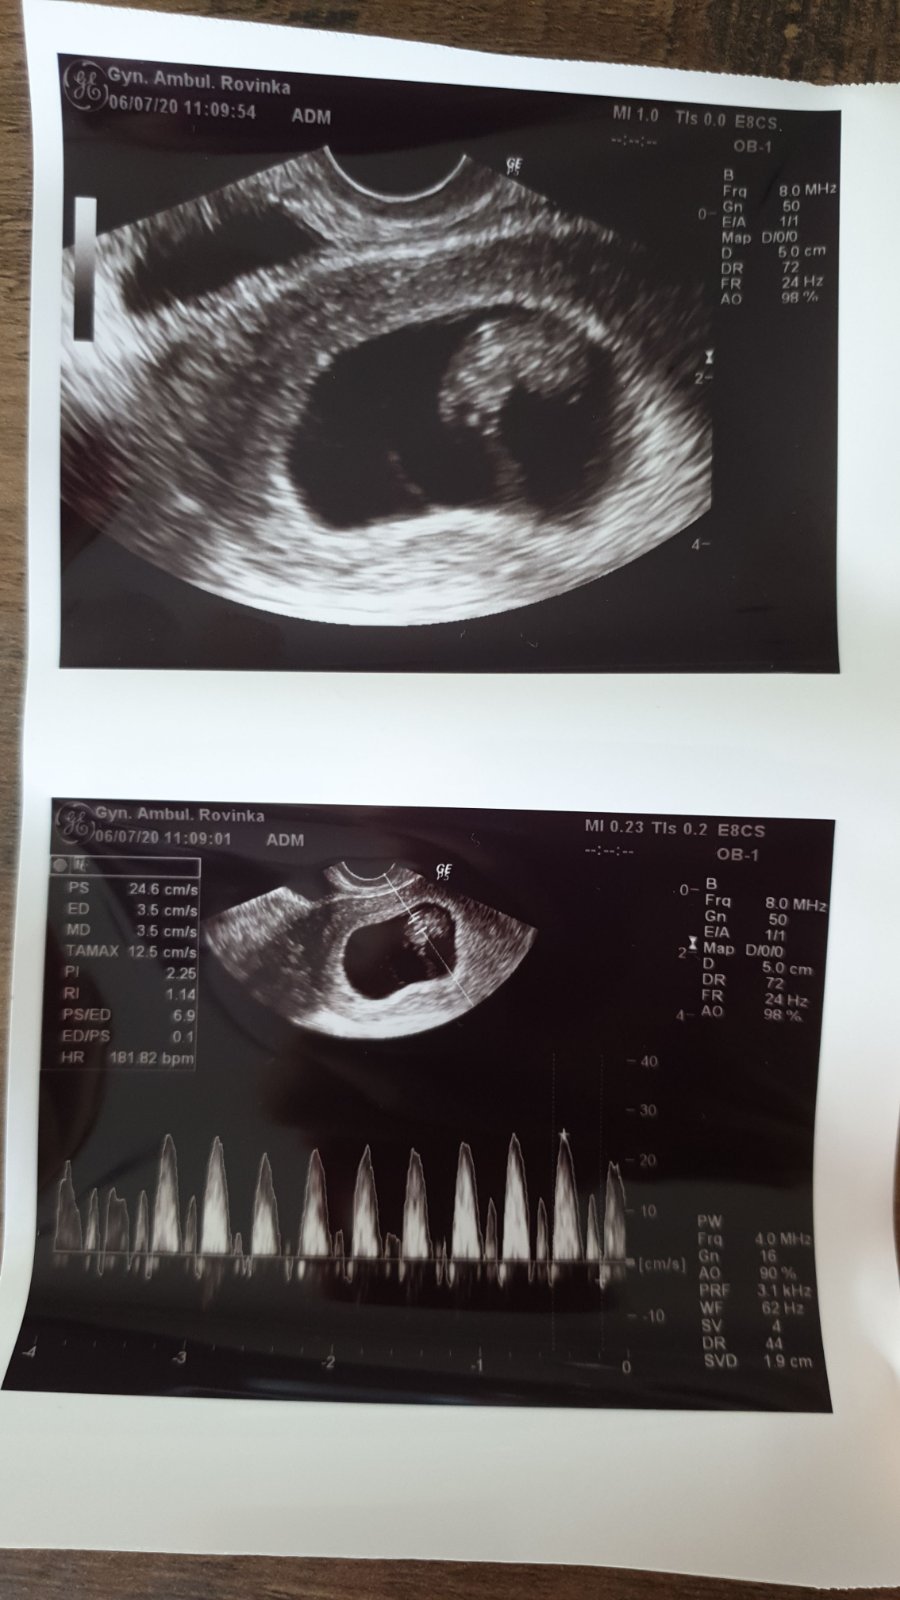

@efran takze ja som dnes 8+4 a takto! Srdiecko dnes bilo 182bpm. A zaciname vyzerat ako baby! Som rada ze tato debata tu ide celkom!